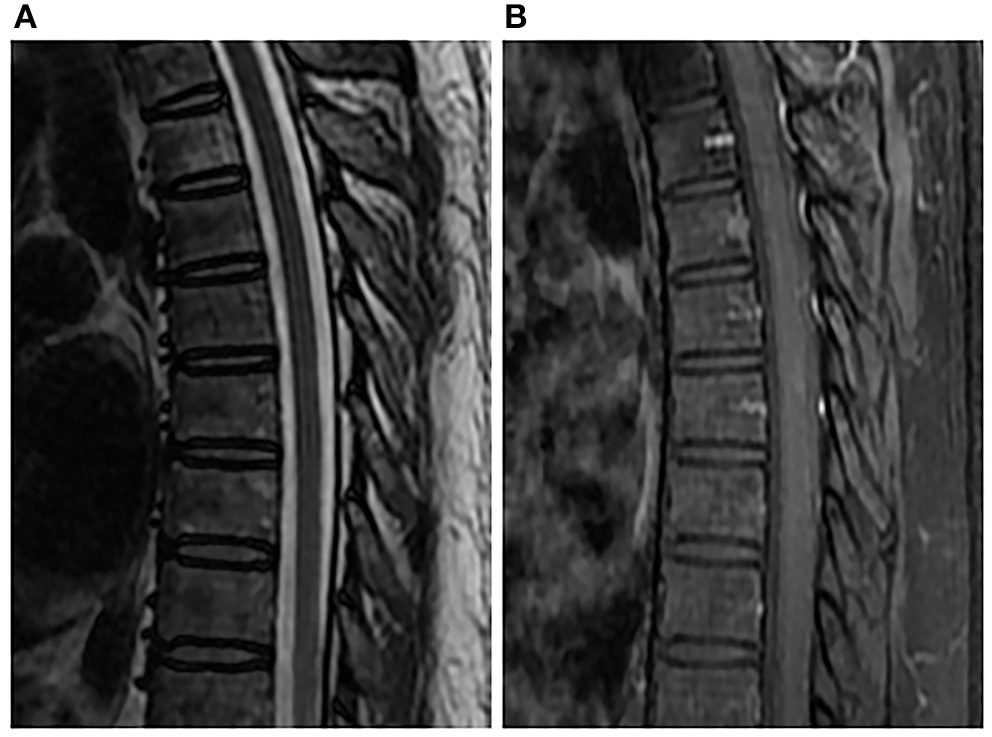

Figure 3

Spinal MRI performed 6 months after penicillin therapy. Sagittal T2-weighted image (A) and enhanced T1-weighted image (B) showed normal spinal cord.